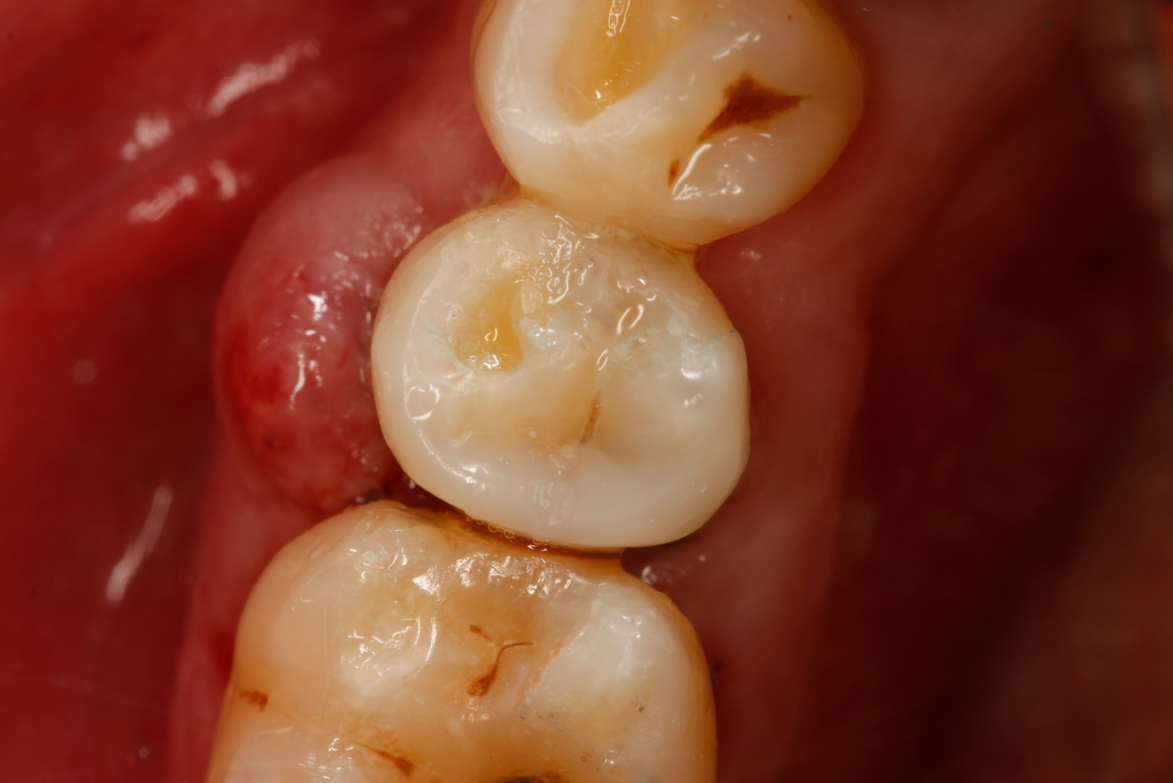

Fig 32. Preparation is completed, caries are removed, sand blasting with potassium carbonate is performed, and matrix band is placed.

Figure 32